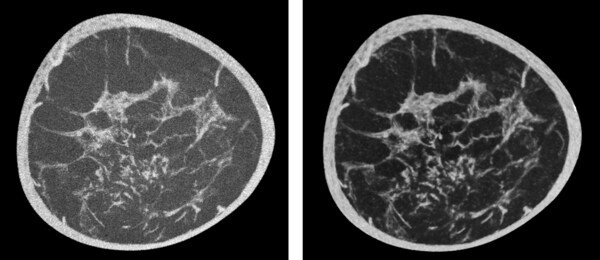

Koning Corporation Unveils Revolutionary AI-Enhanced Software to Boost Breast CT Image Quality

Koning Corporation, a global leader in breast computed tomography (CT) technology, is thrilled to announce the launch of its breakthrough Artificial Intelligence (AI) software, designed to enhance image quality significantly. The upgrade to their software system is set to provide unparalleled clarity in breast imaging, promising a game-changing impact on the early detection and treatment of breast cancer....